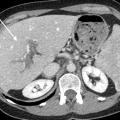

Les maladies vasculaires du foie sont des maladies rares et leur diagnostic peut parfois être difficile, tardif, conduisant à un retard de prise en charge délétère pour le malade. Il est le plus souvent multidisciplinaire, faisant intervenir au premier plan le clinicien mais également le radiologue et l’anatomopathologiste.

Le syndrome de Budd-Chiari (SBC) est une affection rare caractérisée par une obstruction du drainage veineux hépatique, commençant au niveau des veinules hépatiques jusqu’à la partie terminale de la veine cave inférieure. Il peut se manifester par un tableau d’hépatite fulminante, notamment en cas d’obstruction complète des trois…

Les atteintes possibles des petits vaisseaux du foie sont au nombre de quatre (fig. 1)  :la maladie vasculaire porto-sinusoïdale (MVPS)  ;le syndrome d’obstruction des sinusoïdes, appelé également «  maladie veino-occlusive  », caractérisé par l’obstruction des sinusoïdes et des veinules hépatiques par des…

La thrombose de la veine porte (TVP) se caractérise par l’obstruction, le plus souvent par un thrombus, de la veine porte et/ou de ses branches portales (droite et/ou gauche). Cette obstruction peut être partielle ou complète, récente (moins de six mois) ou chronique (plus de six mois) et peut également affecter les vaisseaux…